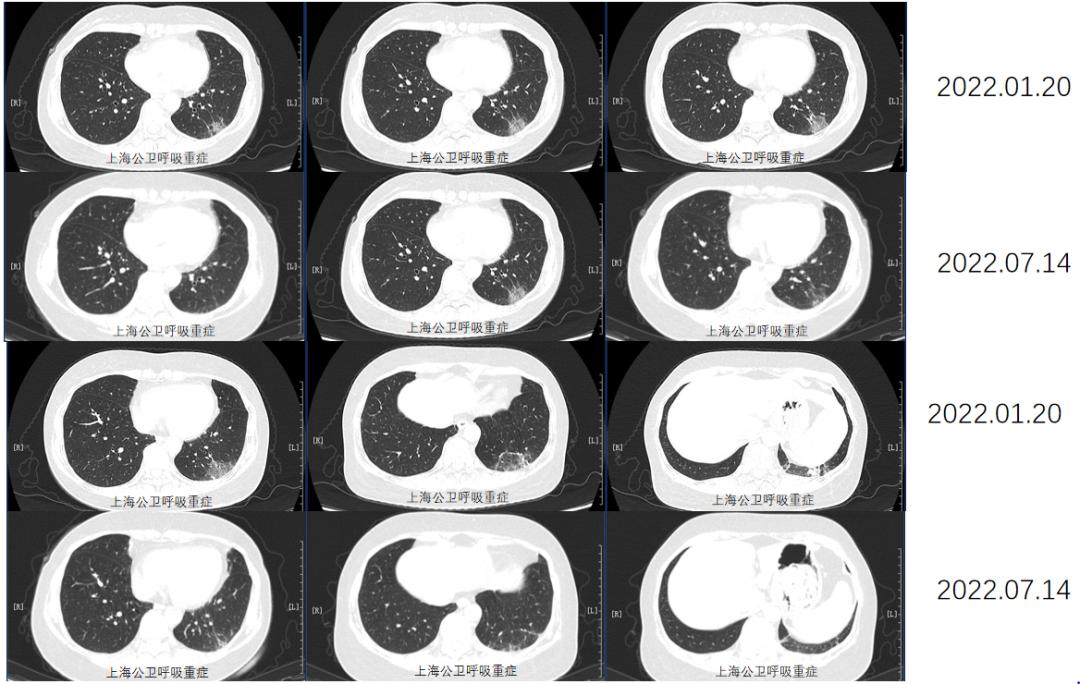

同时给予激素治疗,加用甲强龙40mg,后序贯口服强的松40mg口服,逐渐减量,于2022.1.20及2022.7.14分别复查胸部CT,病灶明显吸收好转。

胸部CT:两肺下叶间质性肺炎复查,对比前片2022-10-25日稍好转,请随访。甲状腺结节,建议彩超检查。

本例患者,第一次入院时胸部CT提示ILD,抗核抗体系列Jo1阴性,无关节不适症状,经TBCB检查,肺部病理考虑NSIP,规律给予激素治疗9月后,停药2月出现右手小指、掌指关节及双侧膝关节麻木、疼痛,抗核抗体系列提示Jo1阳性,CT提示肺部病灶游走新发病灶,肌炎谱检查,仅Jo1阳性,无雷诺现象,无技工手、发热、肌炎症状,无关节炎表现,未行关节X光片检查,以除外其它结缔组织疾病所致关节损害。行肌肉活检,未见肌纤维肿胀,肌纤维间少量炎细胞浸润,伴局灶出血,诊断抗合成酶综合征,于激素应用基础上加用硫唑嘌呤口服治疗后,肺部CT提示肺部病灶好转,关节疼痛症状缓解,后期仍需动态随诊影像学检查、肺功能评定、肌炎谱检查。